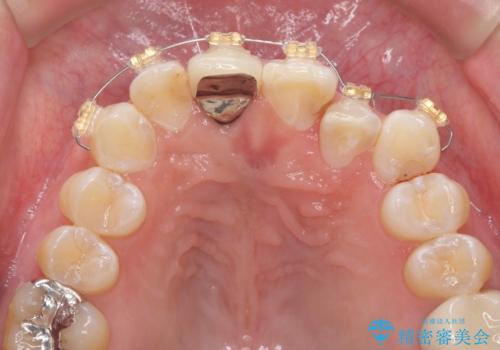

- インビザライン +部分ワイヤー矯正

- 奥に引っ込んでいる前歯を矯正治療で並べたい!色の気になる前歯のクラウンをやり替えたい!と希望され来院されました。

奥に位置している前歯を部分ワイヤー矯正ののちマウスピース矯正インビザラインで並べ、矯正治療後に審美的なジルコニアクラウンを作製していきます。